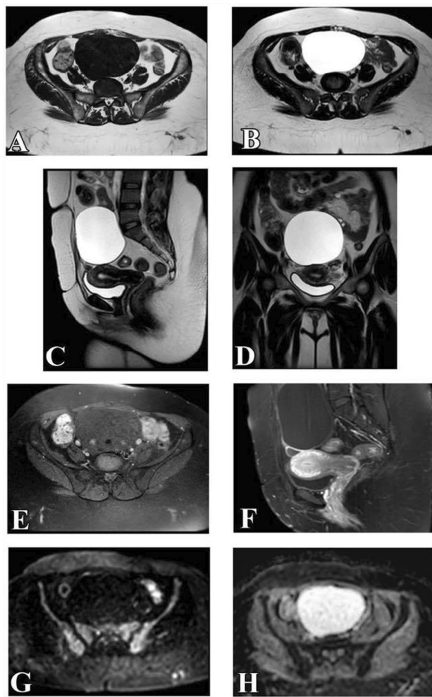

来自曼苏拉大学医学院(Dina EL-Metwally等)的研究团队在《Egyptian Journal of Radiology and Nuclear Medicine》发表的重要研究,对此给出了肯定答案。研究人员创新性地采用1.5T MRI设备,通过标准化扫描方案(包含T2WI、DWIb=1000、ADC值测量及增强T1WI等序列),对50例患者56个附件肿块进行前瞻性评估。研究首次系统验证了O-RADS MRI评分在non-DCE-MRI中的诊断效能,为临床提供了一种更高效的决策工具。

关键技术方法包括:1)多参数MRI扫描(T1/T2加权、DWI、ADC映射);2)双盲阅片(由3年与14年经验的放射科医师独立评估);3)O-RADS MRI标准化评分(基于肿块形态学、增强特征及扩散特性);4)病理学对照(54例手术标本+2例两年随访)。

MRI特征分析

研究揭示恶性肿块的典型标志:93.3%存在强化实性成分(vs 良性7.6%),96.7%表现扩散受限(ADC值0.942±0.24 vs 良性1.79±0.15),70%伴腹膜种植。这些发现为影像鉴别提供了客观依据。

O-RADS分类表现

肿块风险分层显示:80.8%良性归为O-RADS 2(如单纯性囊腺瘤),73.3%恶性归为O-RADS 5(如高级别浆液性癌)。值得注意的是,当将O-RADS 3(如黏液性囊腺瘤)视为恶性时,系统灵敏度达100%且阴性预测值(NPV)完美,这对排除恶性肿瘤具有重要临床价值。